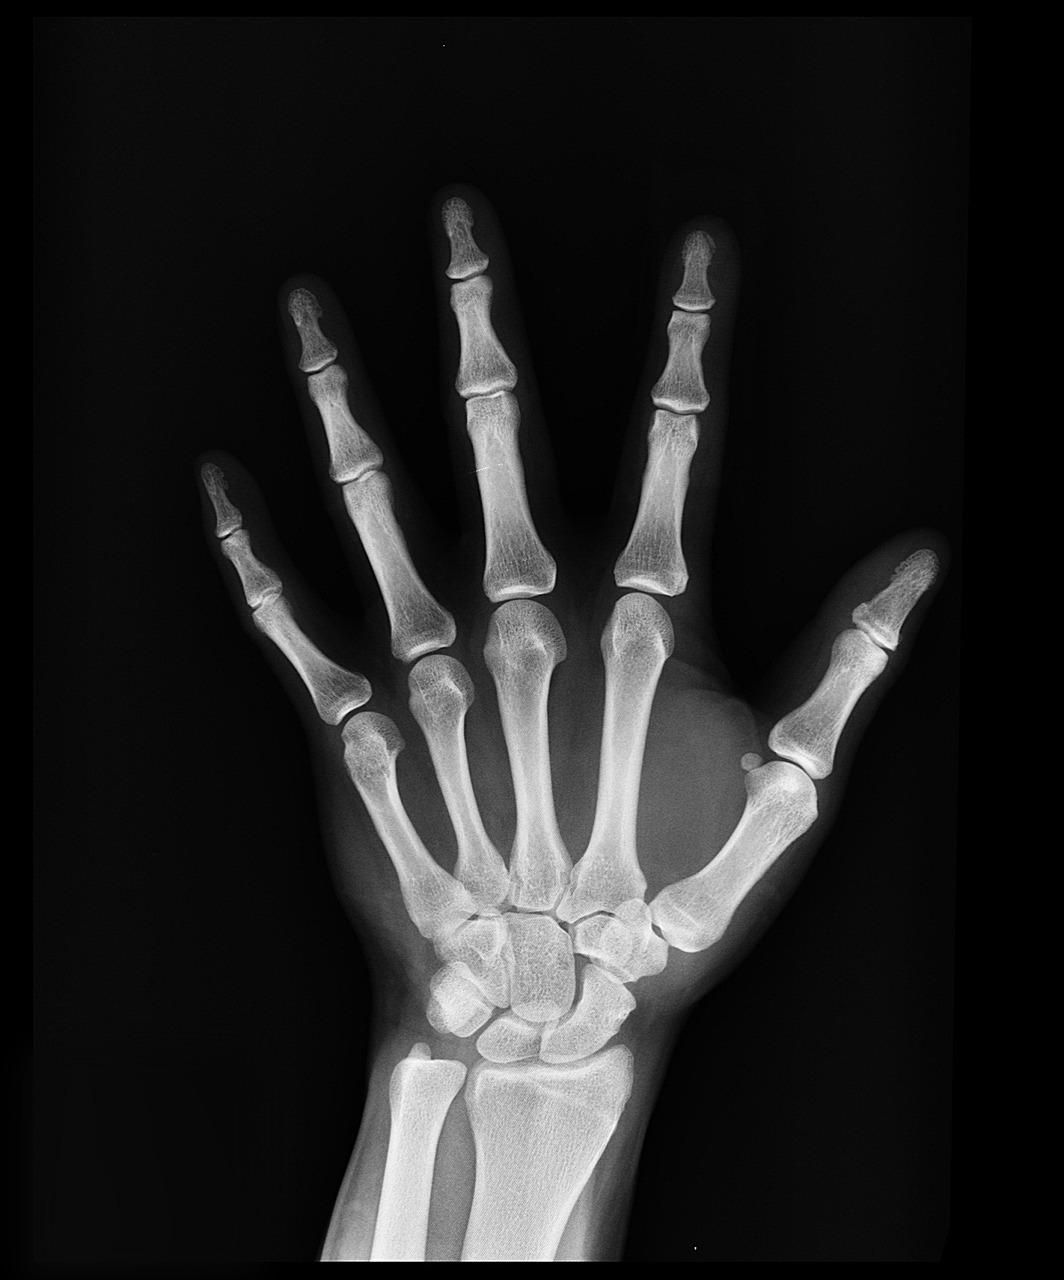

- X-ray 검사

관절의 뼈 구조를 확인하여 관절염이나 손상 여부를 판단합니다. 관절의 퇴화 정도를 확인하는 데 유용합니다.